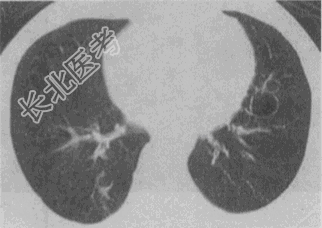

- 单项选择题患者女,23岁, 咳嗽咳痰反复发作,根据CT图像, 最可能的诊断是

A、支气管扩张并感染

B、多发肺气囊

C、多发性肺囊肿并感染

D、多发性肺脓肿

E、大叶性肺炎